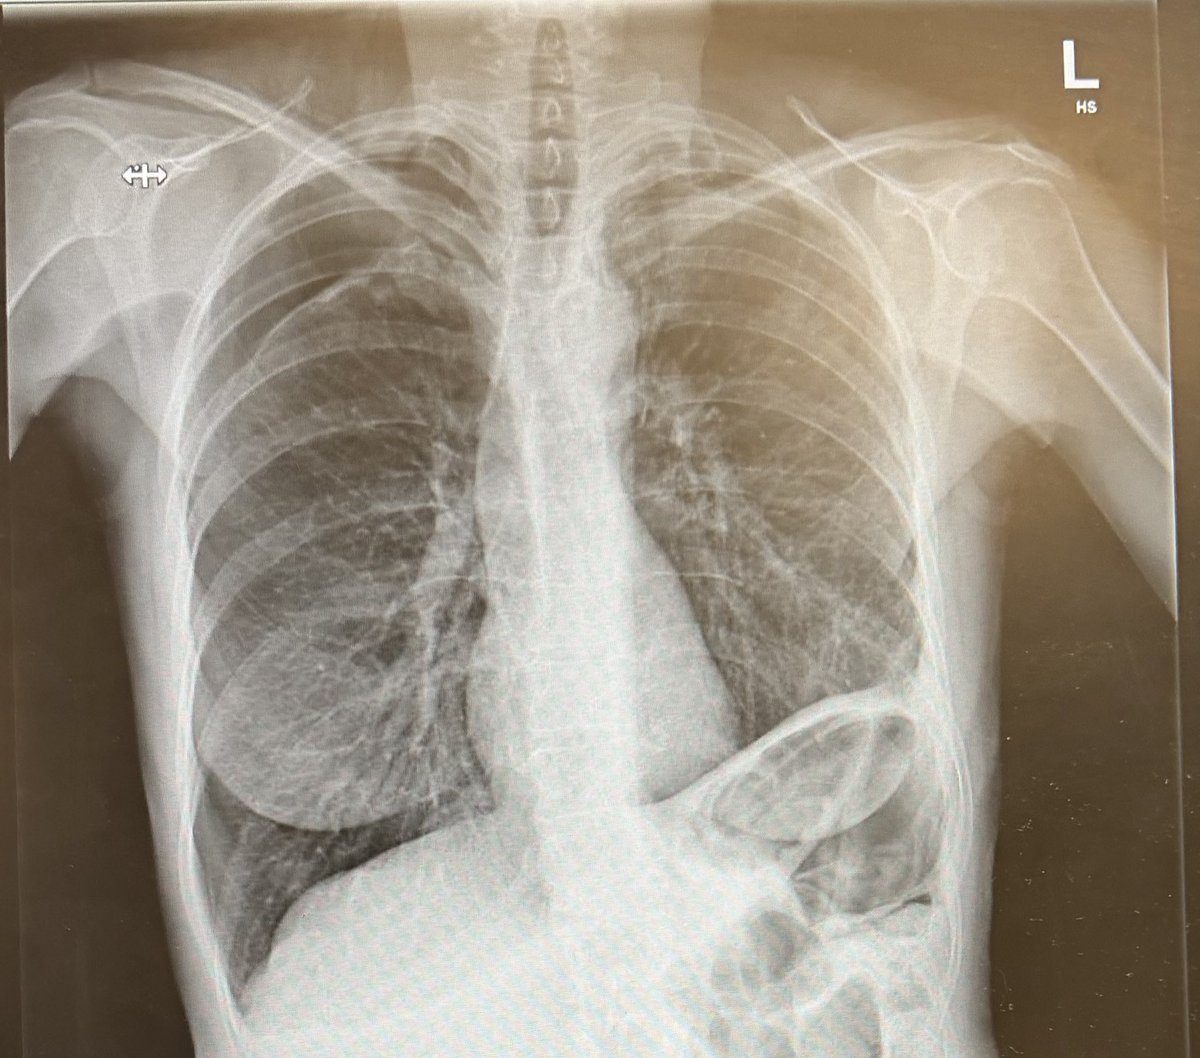

What's the diagnosis? #MedTwitter #FOAMed Dr. Priyam Bordoloi अहिरावण Dr. Shiv_Kumar Dr. Akhil 🇮🇳 Dr. El_Nino